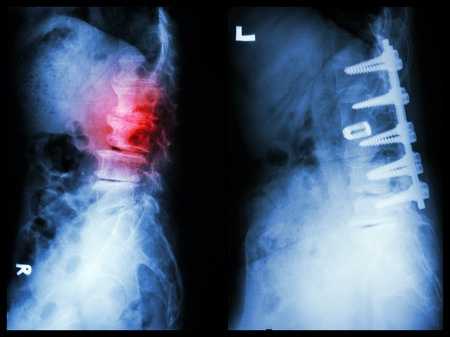

Рис. 1. Пациент В. Титановая блок-решетка без наполнения через 1 месяц (А) и через 12 месяцев (Б) после операции. Нарастание «продавливания» имплантатом кости с увеличением перифокального склероза и резорбции костной ткани

К концу первого месяца после операции (табл. 2) в обеих группах с одинаковой частотой выявлены умеренные реактивные изменения паравертебральных тканей при отсутствии признаков прогрессирования костной деструкции. Вместе с тем, в группе 1 у всех пациентов обнаружено “продавливание” меша в тела блокируемых позвонков на глубину до 1 мм и наличие перифокальной резорбции с отграниченной зоной склероза. В трети случаев у пациентов этой группы угол кифоза увеличился на величину более 5 ° , что не может быть расценено как ошибка измерения. В группе 2 - во всех случаях имплантат плотно соприкасался с телами позвонков без перифокальной резорбции и без нарастания деформации; склеротическая реакция блокируемых тел отмечена у 2 пациентов (8,7%).

Рис. 2. Пациент У. Титановая блок-решетка с аутокостью через 6 месяцев (А) и через 12 месяцев (Б.) после операции. Отсутствие зоны резорбции вокруг имплантата без выраженного склероза, полная ассимиляция трансплантата с ложем

При дальнейшем исследовании в сроки 3 мес. и 6 мес. после операции (табл. 3) в обеих группах отсутствовали реактивные изменения в паравертебральных мягких тканях, при этом в группе 1 отмечено нарастание проявлений “вертикальной нестабильности” в виде дальнейшего “продавливания” сеткой тел позвонков на глубину до 3,07±0,8 мм к 3 месяцу и до 3,78±0,7 мм к 6 месяцу с резорбцией и склерозом костного ложа у всех пациентов; больше, чем у трети больных угол деформации в сагиттальной плоскости увеличился более, чем на 5 ° ; лишь в единичных наблюдениях отмечены признаки формирования костного блока в зоне спондилодеза, в то время, как в группе 2 признаки формирования блока между наполнителем меша и реципиентным костным ложем обнаружены уже у большинства пациентов.

Через 12 месяцев после операции (табл. 4) в группе 1, несмотря на более выраженную резорбцию (6,43±1,06 мм), сагиттальный профиль позвоночника стабилизируется в сравнении с предыдущим периодом, при этом частичная стабилизация позвоночника появляется на фоне выраженного склероза за счет массивных краевых костных разрастаний. В то же время, в группе 2 у всех больных стабильность передней колонны обеспечивается полной ассимиляцией трансплантатов с ложем позвонков.